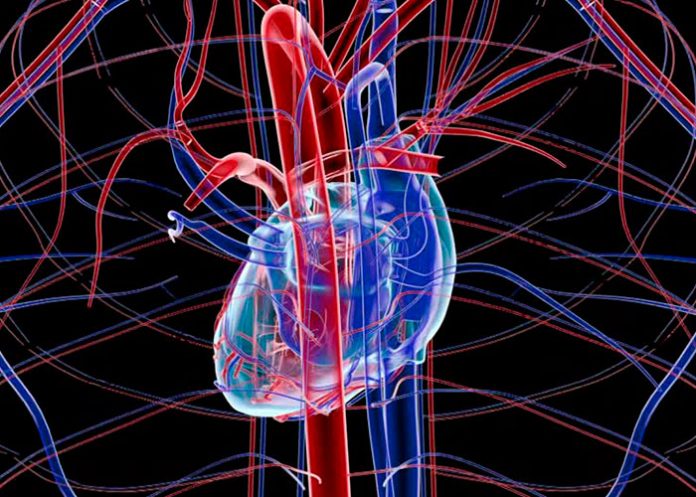

Una molécula producida durante el ayuno o la restricción calórica tiene efectos antievejecimiento en el sistema vascular, lo que podría reducir la aparición y gravedad de las enfermedades humanas relacionadas con los vasos sanguíneos, como las enfermedades cardiovasculares, según un estudio dirigido por la Universidad Estatal de Georgia.

“La parte más importante del envejecimiento es el vascular”, afirma. Cuando las personas envejecen, los vasos que suministran diferentes órganos son los más sensibles y están más sujetos al daño del envejecimiento, por lo que es muy importante estudiar el envejecimiento vascular. Este estudio se centra en qué tipo de cambios ocurren y cómo prevenir este envejecimiento.